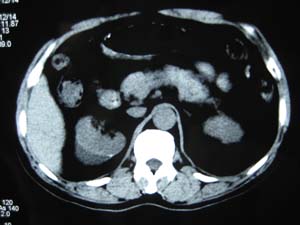

标题: CT17067:男,50Y右上腹痛一个月,无外伤史 [打印本页]

标题: CT17067:男,50Y右上腹痛一个月,无外伤史

右肾包膜下积液,包膜可见线状钙化

不除外慢性血肿

右肾包膜下积液(陈旧性血肿?),包膜可见线状钙化。

右肾包膜下积液,包膜可见线状钙化。左肾可疑血管平滑肌脂肪瘤,把窗调宽一些.